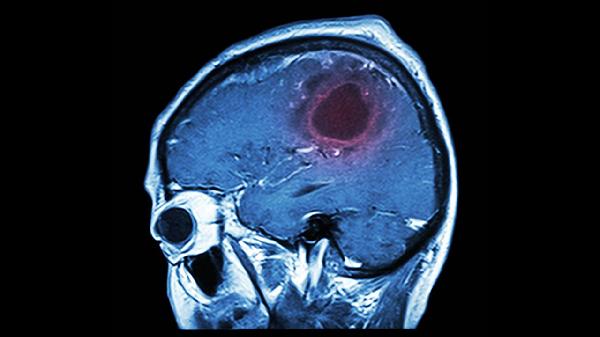

局限性血栓引起的輕微記憶障礙,通過代償機制可能完全恢復(fù)。大面積腦梗死損傷海馬體等記憶中樞時,恢復(fù)難度顯著增加。臨床常用彌散加權(quán)成像評估缺血半暗帶范圍,指導(dǎo)溶栓決策。

建議患者保持規(guī)律作息與適度社交活動,每日進行30分鐘有氧運動如快走或游泳,促進腦部血液循環(huán)。飲食采用地中海模式,多攝入藍莓、堅果等抗氧化食物,限制飽和脂肪酸攝入。家屬可通過老照片回顧、日記共讀等方式激發(fā)情景記憶,避免過度代勞日常事務(wù)以維持認知功能。定期復(fù)查頭顱磁共振監(jiān)測腦血流灌注情況,配合中醫(yī)針灸治療可能改善記憶提取功能。